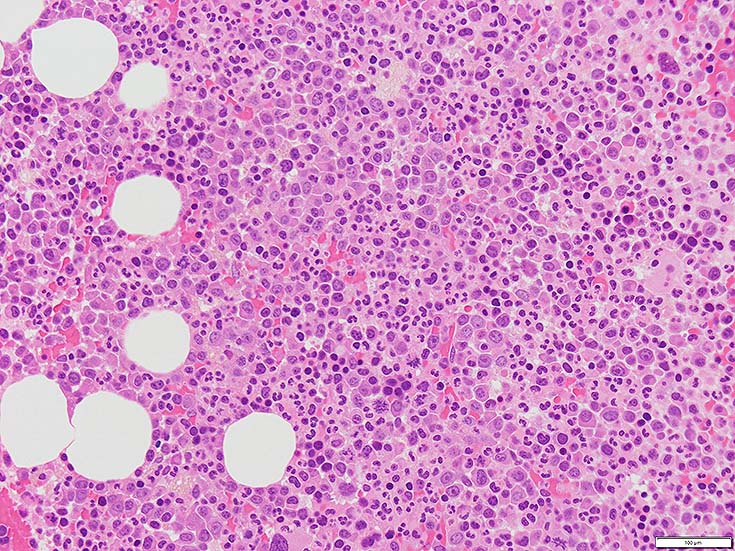

初診時の骨髄組織所見

HE染色および, Naphtol-ASD-CAE染色した骨髄クロット組織標本-->Naphtol-ASD-CAE染色, 載せガラス法のページをみる.

70-80%のhypercellular marrow. 3系統造血細胞が認められる. Naphtol-ASD-CAE染色で赤色にそまる顆粒球系細胞増生が顕著な骨髄組織.

promyelocytesなど幼若顆粒球系細胞の集簇がみられるが, 分葉好中球他, 成熟顆粒球(Naphtol-ASD-CAE染色は薄く染まる傾向あり)も多く認められacute leukaemiaの所見ではない.

単球(Naphtol-ASD-CAE染色陰性)が密に増殖する所見は骨髄組織には認められない(*1)